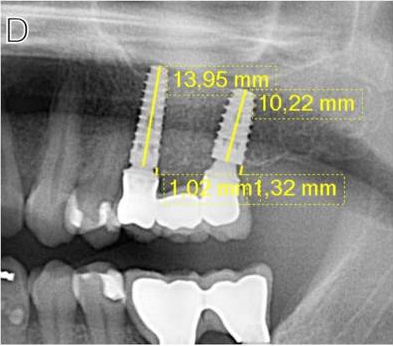

Marginal bone loss (MBL) around dental implants is a significant concern in implant dentistry as it can affect the long-term success and stability of the implants. A new study concluded that stated that as the duration of prosthetic delivery time increases following the surgical placement of dental implants, the risk of marginal bone loss also increases.